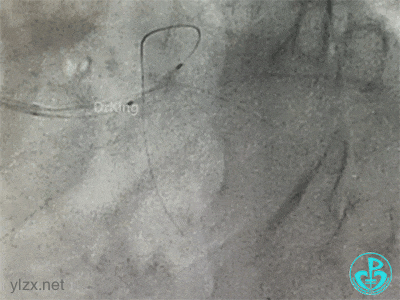

左主干分叉病变采取Crush双支架术式,回旋支开口植入支架,前降支开口球囊挤压后左主干到前降支植入支架(Crush双支架术式)。

导丝准备穿支架网眼Rewire回旋支时患者血压继续下降。去甲肾上腺素微量泵剂量逐渐增大至25ml/h,立即置入IABP,血压回升后再继续操作。

导丝Rewire回旋支,非顺应性球囊分别后扩张前降支和回旋支支架,对吻扩张。